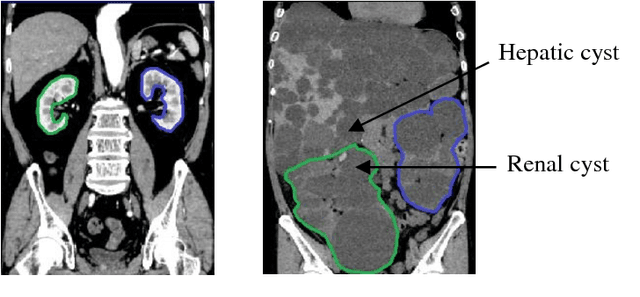

Abstract:Autosomal Dominant Polycystic Kidney Disease (ADPKD) characterized by progressive growth of renal cysts is the most prevalent and potentially lethal monogenic renal disease, affecting one in every 500-100 people. Total Kidney Volume (TKV) and its growth computed from Computed Tomography images has been accepted as an essential prognostic marker for renal function loss. Due to large variation in shape and size of kidney in ADPKD, existing methods to compute TKV (i.e. to segment ADKP) including those based on 2D convolutional neural networks are not accurate enough to be directly useful in clinical practice. In this work, we propose multi-task 3D Convolutional Neural Networks to segment ADPK and achieve a mean DICE score of 0.95 and mean absolute percentage TKV error of 3.86. Additionally, to solve the challenge of class imbalance, we propose to simply bootstrap cross entropy loss and compare results with recently prevalent dice loss in medical image segmentation community.